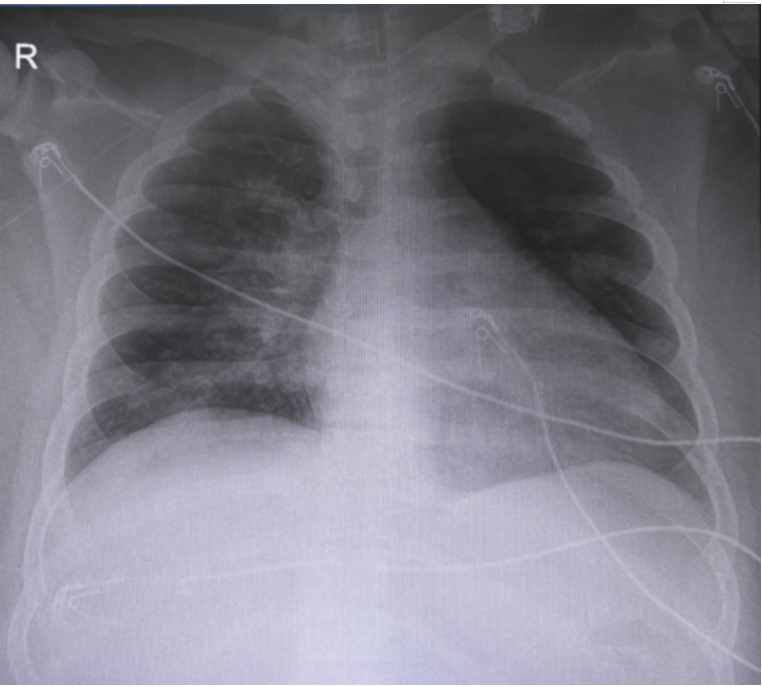

患者入MICU后胸片提示双肺炎症渗出为主(图2)。胸部CT示大面积实变,以重力依赖区为主(视频1)

图片

图2  患者入MICU后胸片

结合患者胸部CT和胸片可以发现,患者的肺容积明显下降,膈肌较正常人上移,双肺重力依赖区大面积实变。流行病学数据表明,肥胖患者较体重正常患者更容易患ARDS, 这往往与肥胖患者的病理生理学特点相关,图3总结了肥胖患者病理生理特点及低氧的原因。